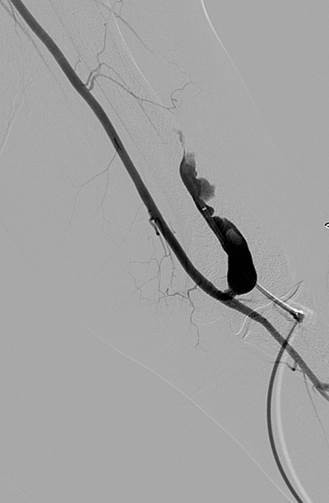

Thrombosed AV graft with stenosis at venous anastomosis.

AngioJet DVX catheter in AV graft.

Imaging post-AngioJet System activation in venous side of AV graft.

Imaging post-AngioJet System activation in arterial side of AV graft.